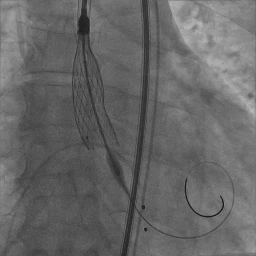

瓣膜完全释放

瓣膜释放后主动脉根部造影

瓣膜植入后球囊后扩张

球囊扩张后主动脉根部造影

术后第二日复查超声心动图:EF39%,TAVI术后 人工支架瓣膜功能正常,瓣周漏(少量),左心增大,二尖瓣反流(轻度),三尖瓣反流(轻度),升主动脉内径增宽。

患者取平卧位,局麻镇静,颈内静脉置入中心静脉置管,测中心静脉压3cmH2O,左侧桡动脉穿刺置管监测动脉压力。术区无菌消毒铺巾,穿刺右侧桡动脉并置入6F鞘管,超声引导下穿刺双侧股动静脉,右股动脉预置两把Proglide缝合器,左侧股动静脉留置6F鞘管。将Lunderquist加硬导丝送至升主动脉,沿加硬导丝送20F GORE动脉鞘管。将临时起搏漂浮电极经右股静脉送至右室心尖部位,测试起搏器工作良好。予肝素6000单位,ACT大于250s。经左股动脉置入6F猪尾导管,在释放体位下行主动脉根部造影。经右侧桡动脉送脑保护装置分别在左颈总动脉、头臂干动脉释放保护。经右侧股动脉送入6F JL4.0造影导管造影提示:左前降支未见明显狭窄,TIMI血流III级;回旋支未见明显狭窄,TIMI血流III级。送入6F JR4.0造影导管造影提示:右侧冠脉未见明显狭窄,TIMI血流III级。在AL2导管指引下,直头导丝跨瓣至左心室,沿导丝送猪尾导管至左心室,测得跨瓣压差50mmHg。经猪尾导管送入塑形后的加硬导丝送至左心室内,沿加硬导丝送启明L26主动脉瓣系统至主动脉瓣处,在释放体位下释放至工作状态,经猪尾导管行主动脉造影示瓣膜定位良好。继续完全缓慢释放瓣膜。送入20×40mm球囊至主动脉瓣,在180次/分起搏下,收缩压下降至50mmHg时行球囊扩张,扩张无明显腰征。主动脉造影示瓣膜支架膨胀良好,微量瓣周漏。撤出输送系统。经胸超声评估主动脉瓣位为人工瓣回声,位置固定,瓣叶活动良好。主动脉造影提示主动脉无夹层、出血。行造影提示腹主动脉、髂动脉、股总动脉未见明显异常,缓慢撤出20F大鞘管,缝合右侧股动脉穿刺点,保留右侧临时起搏器并固定良好。